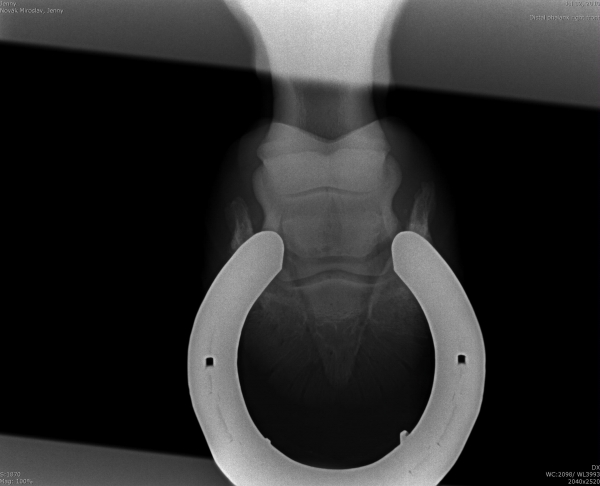

Podotrochleóza

Sam - kladrubský hřebec s laminitídou a výhřezem kopytní škáry, teď krásně chodící a to hlavně díky velké pomoci podkováře, p.Schmidta